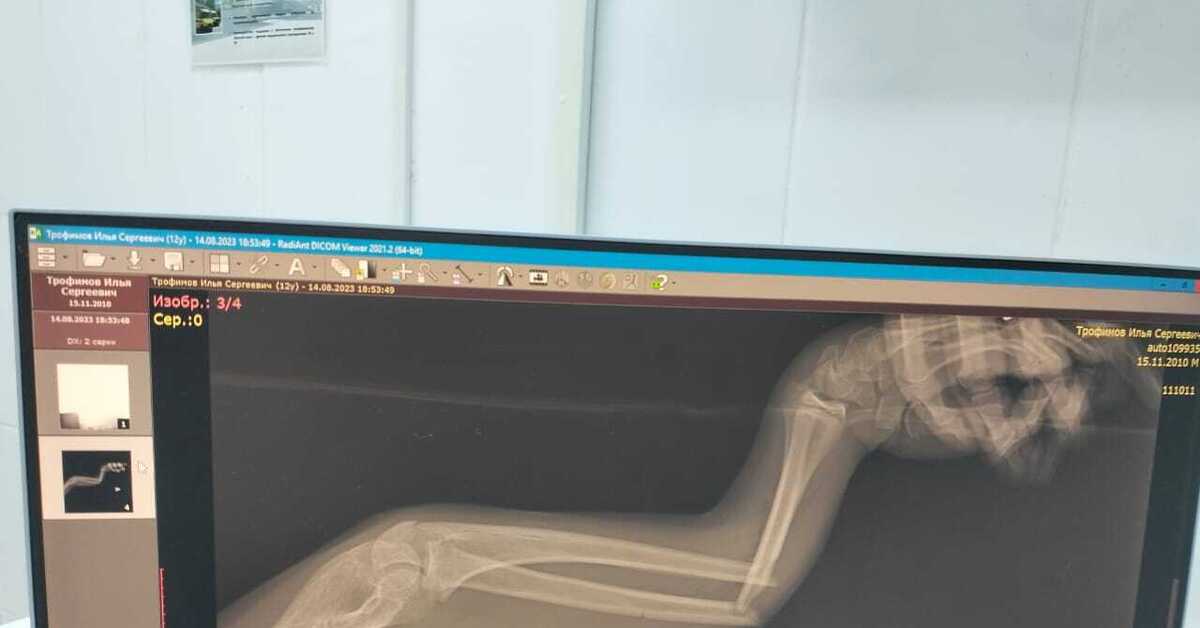

Открытый Перелом Руки Фото

Открытый Перелом Руки Фото 109 фотографий